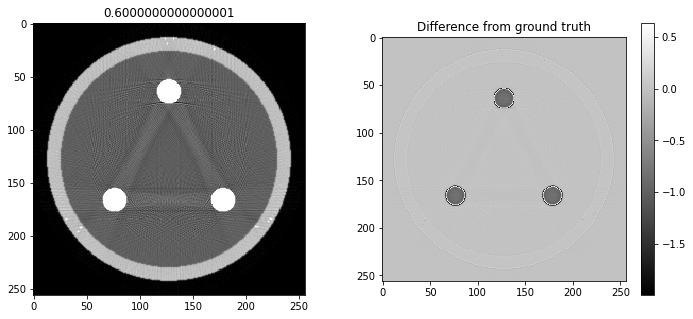

# Question 12

search = np.linspace(0,1,11)

for alpha in search:

rec = out+alpha*reproj

f,ax = plt.subplots(1,2,figsize=(12,5))

ax[0].imshow(rec,vmin=0,vmax=0.5)

ax[0].set_title(alpha)

im = ax[1].imshow(img[80]-rec)

f.colorbar(im,ax=ax[1])

ax[1].set_title('Difference from ground truth')

plt.show()